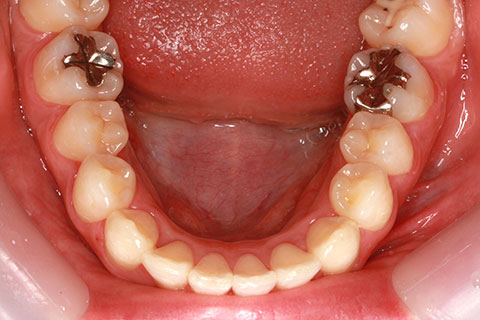

症例

治療前

治療後

- 年齢・性別

- 30歳女性

- 治療期間

- 3年0ヶ月

- 抜歯

- 上下左右4番抜歯

- 治療費

- 110万円

- 備考

- マルチブラケットを用いた矯正治療

- 治療内容

- 上下顎前突を4本抜歯にて矯正治療

- 施術の副作用(リスク)

- 表側矯正と比較して、歯根の角度を確立する「トルク」の力がかかりにくい。